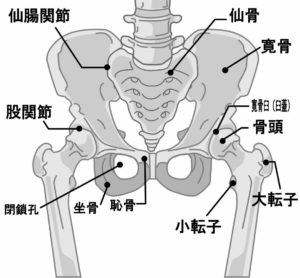

出産時に骨盤が大きく開かれますが、その時の力の入れ方や普段の体の使い方の癖などで骨盤が大きく歪み、出産後そのまま残る場合があります。

骨盤全体の歪みは腰痛などの原因にもなりますし、骨盤の一部(恥骨部)の歪みが大きいと生理痛や性交痛や尿漏れと言った症状につながりやすくなります。

大まかに話しますと生理時に骨盤は閉じるのですが、恥骨に歪み(ズレ)があるとその周辺の組織によじれが生じます。そうすると内臓も負担を受けますし、骨盤もすんなりと閉じてくれないので痛みや不快感を感じるようになります。

さらに尿を漏らさないために尿道括約筋ががんばんるのですが、骨盤(恥骨部)の歪みによってこの括約筋もうまく力が入らなくなり、尿が漏れやすくなります。

そしてその恥骨部は頭のこめかみ部分(蝶形骨)と連動していますので、歪みが大きいと生理で骨盤が動くときに頭痛や目のトラブルの原因になります。

このこめかみの骨(蝶形骨)は目の裏で左右が繋がっている骨なので目に対する影響もありますが、他に体中の関節の動き、手先足先、内臓、呼吸器系、頚椎など色々と関係していて影響します。